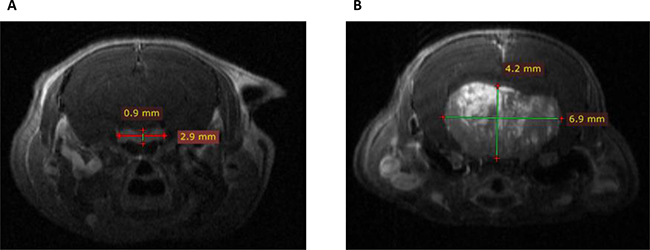

To evaluate in vivo lactotroph tumor development, pituitary MRI was performed in two 18-month-old Prlr–/– female mice as compared to two Prlr+/+ animals (Figure 2). This imaging technology revealed the presence of large heterogeneous T1 enhanced pituitary macroadenomas reaching 6.9 mm of diameter in Prlr–/– females, with cerebral mass effect. This heterogeneous magnetic signal after gadolinium injection suggested the existence of an important neovascularization in the tumor, a process also described in human prolactinomas [15].

Figure 2: Coronal T1 weighted post-gadolinium enhanced Magnetic Resonance Imaging scans in Prlr+/+ and Prlr–/– 18-month-old female mice. (A) Normal pituitary gland in a Prlr+/+ mouse. Pituitary measured 2.9 × 0.9 mm, with a homogeneous signal after gadolinium injection. (B) Representative pituitary imaging in a Prlr–/– mouse revealing heterogenous T1 enhanced pituitary macroadenoma of 6.9 × 4.2 mm of diameter with cerebral mass effect.